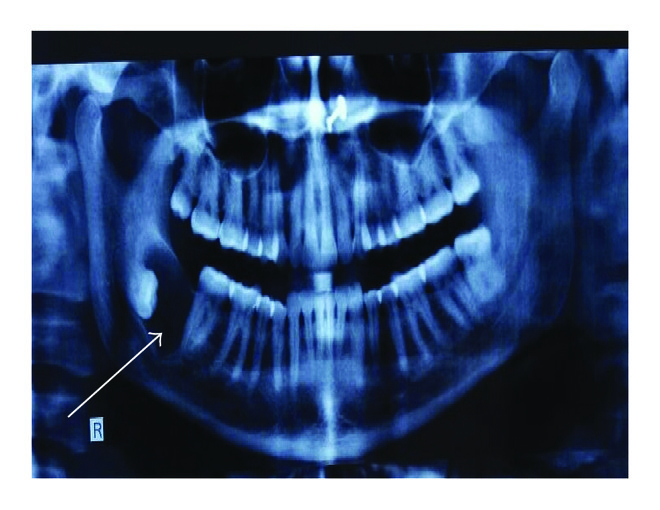

2.2. Case 2

A 38-year-old female complained of swelling since 6 months at right side posterior mandible. Patient stated that the swelling gradually increased in size with pus discharge and no pain. Intraorally, the swelling was 3 × 2 cm in size at right angle region with missing 48. Overlying mucosa appeared smooth, nonerythematous and nontender on palpation. A well-defined radiolucency in relation to crown of 48 was seen in the orthopantomography. A provisional diagnosis of dentigerous cyst and keratocystic odontogenic tumor (KCOT) was made. The cyst was surgically enucleated and the histopathology revealed nonkeratinized stratified squamous cystic epithelial lining, 2-3-cell layer thick, which showed proliferation in few areas associated with underlying inflammation. In the connective tissue cystic capsule, mixed inflammatory cell infiltrates with areas of hemorrhage were evident. A part of the tissue revealed abundant cholesterol clefts in the cystic capsule in association with multinucleated giant cells. Based on this a diagnosis of dentigerous cyst with cholesterol granuloma was made (Figure 2).

(a)

(b)

(c)

(d)